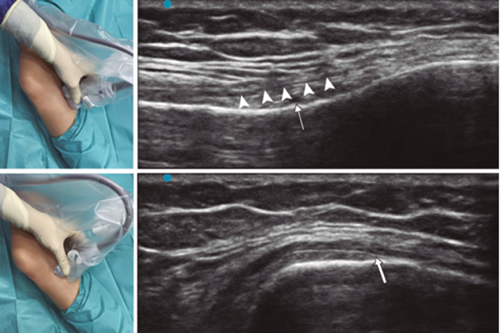

Figure 2